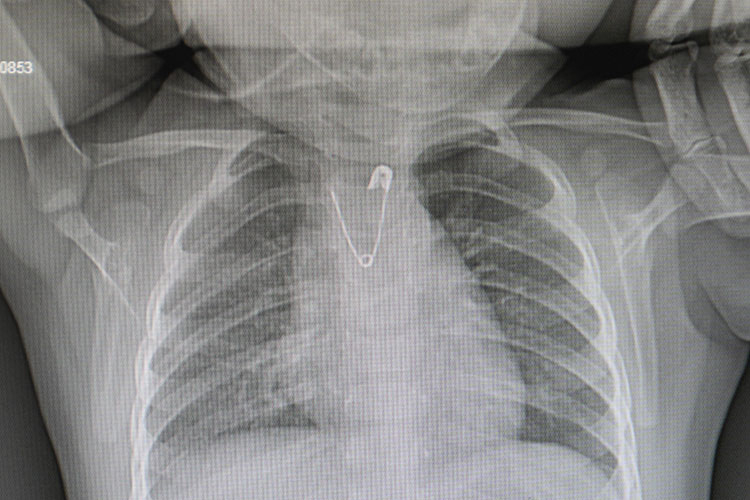

Annenin bu esnada bebeğinin yakasına takılan duanın çengelli iğnesinin olmadığını fark ettiğini ve ailenin bunun üzerine hemen acil servise başvurduğunu belirten Çalışkan, "Bebeğimizin acil serviste çekilen akciğer grafisinde açık ağızlı bir çengelli iğnenin yemek borusunun en dar yeri olan üst kısmı tıkadığını gördük. Bu da çocuğumuzun kusmasına, beslenememesine neden oluyordu. Hemen ameliyathaneye alarak anestezi altında yapılan endoskopi işlemiyle çengelli iğneyi çıkarttık." bilgisini paylaştı.